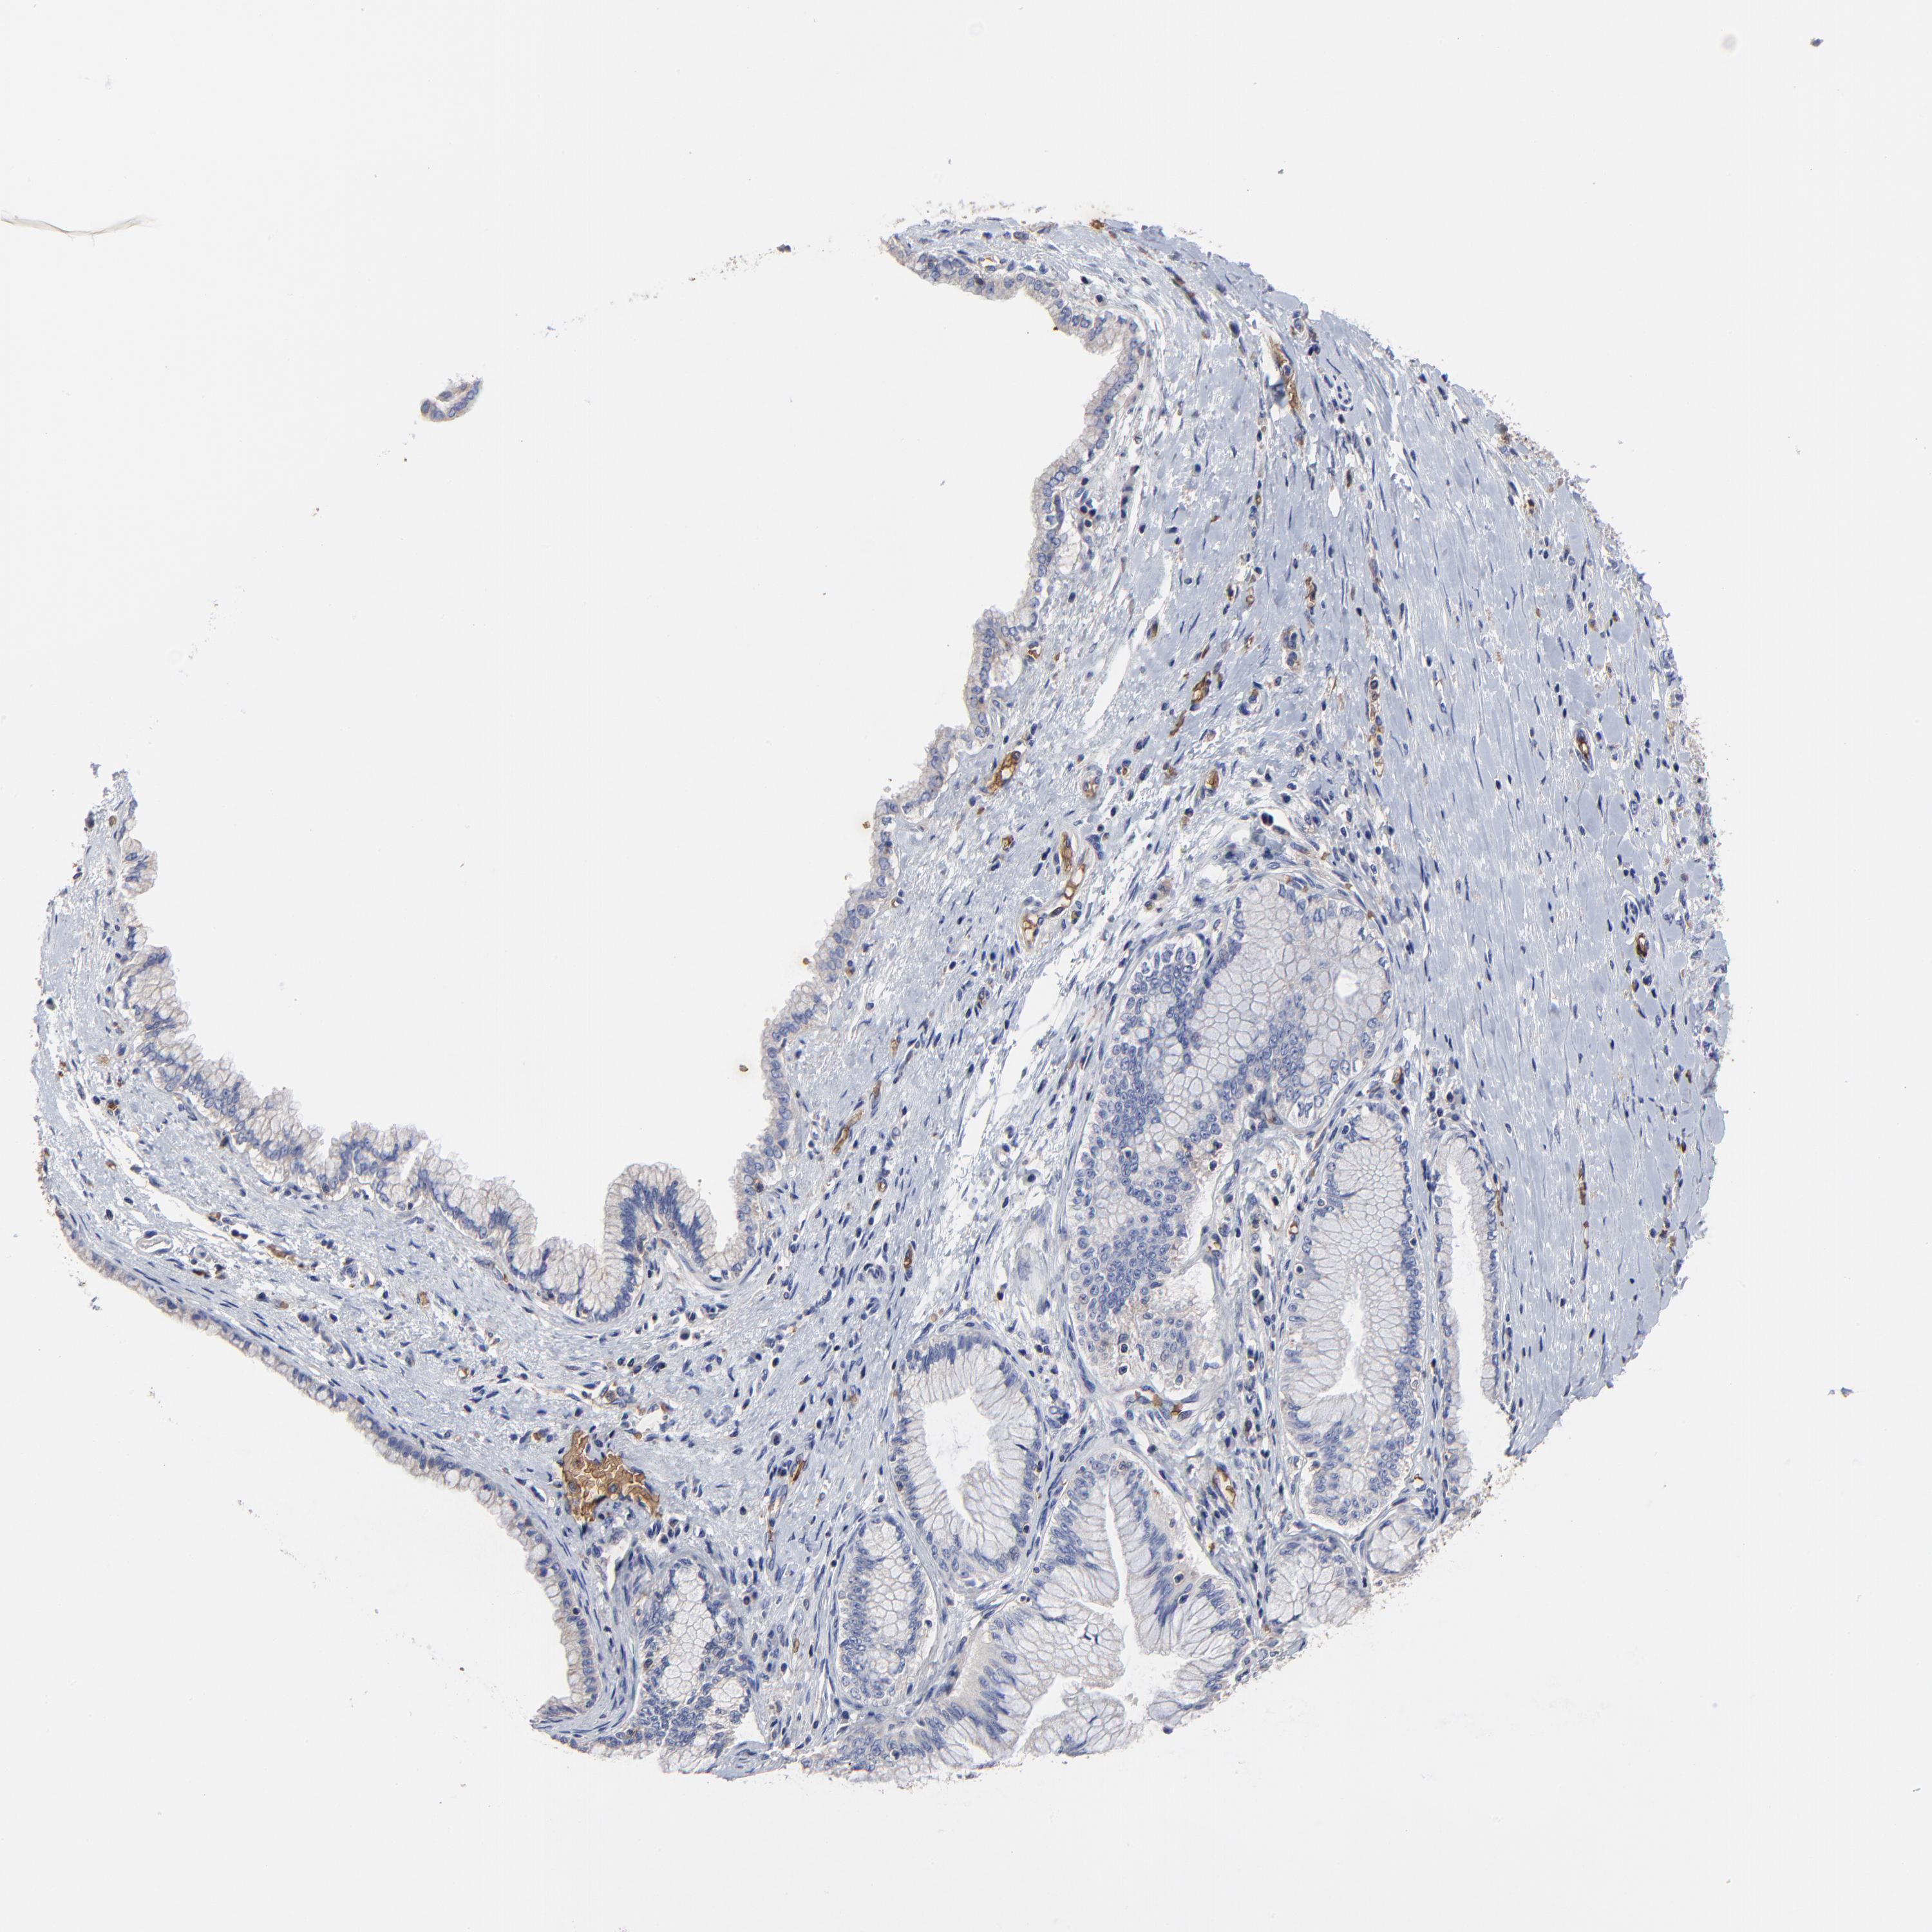

PANCREATIC CANCER - Protein expressioni

A mouse-over function shows sample information and annotation data. Click on an image to view it in a full screen mode. Samples can be filtered based on level of antibody staining by selecting one or several of the following categories: high, medium, low and not detected. The assay and annotation is described here.

Note that samples used for immunohistochemistry by the Human Protein Atlas do not correspond to samples in the TCGA dataset.

Antibody stainingi

Antibody staining in the annotated cell types in the current human tissue is reported as not detected, low, medium, or high, based on conventional immunohistochemistry profiling in selected tissues. This score is based on the combination of the staining intensity and fraction of stained cells.

Each image is clickable and will lead to virtual microscopy that enables deeper exploration of all samples and also displays staining intensity scores, fraction scores and subcellular localization as well as patient and tissue information for each sample.

Antibody HPA001632

Antibody HPA066527

Staining

High

Medium

Low

Not detected

Intensity

Strong

Moderate

Weak

Negative

Quantity

>75%

75%-25%

<25%

None

Location

Nuclear

Cytoplasmic/membranous

Cytoplasmic/membranous,nuclear

Adenocarcinoma, NOS

Adenocarcinoma, metastatic, NOS